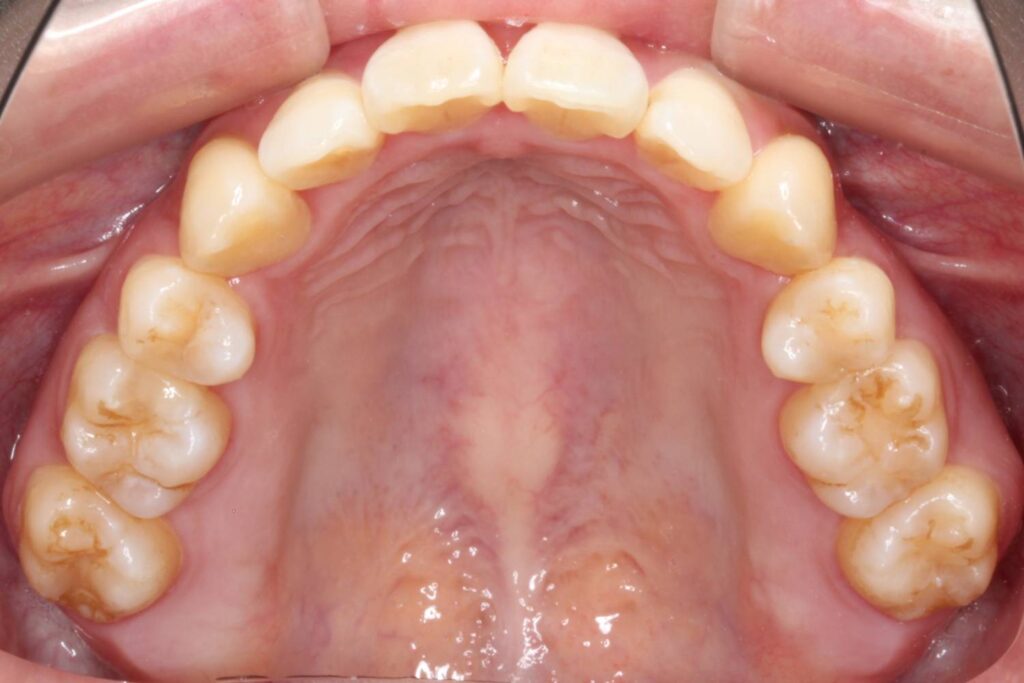

前歯に叢生があり、特に右上の前歯は前方に突出していて目立ってしまっています。

また、上顎の犬歯は「八重歯」と呼ばれる状態で、唇をよく噛んでしまったり、口内炎ができてしまうとのことでした。

奥歯の噛み合わせは、下顎に対して上顎が前方にずれてしまっています。

Before